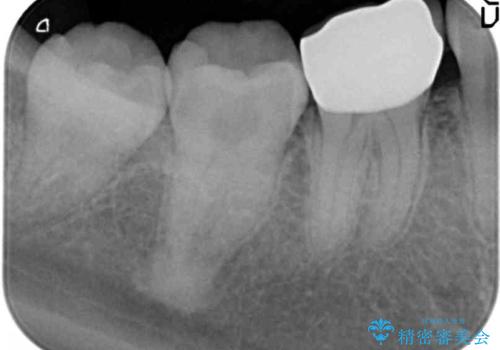

- 笑った際に見える銀歯を白くしたいと希望され来院されました。

銀歯の周囲にも虫歯が見られたのでインレーではなく、耐久性の強いフルジルコニアクラウンでの治療を計画します。

銀歯の周囲に虫歯が再発していたり、内部に虫歯が発生している場合などインレーからクラウン形態へとした方が長期的予後が良い場合があります。